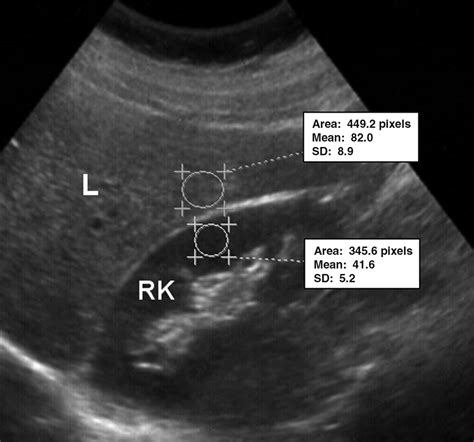

In the world of medical imaging, the liver is typically used as the "benchmark" for brightness. Healthy liver tissue has a specific texture and gray-scale appearance known as isoechogenicity. When an ultrasound technician scans the liver, they compare its brightness to the nearby kidney cortex and the spleen. If the liver appears brighter, darker, or more grainy than normal, it signals a change in the internal composition of the organ. The echogenicity of the liver is a direct reflection of how much sound energy is bouncing back to the transducer, which changes based on the presence of fat, fibrous tissue, or cellular swelling.

Radiologists categorize the liver's appearance into three primary grades based on how the echoes are reflected. Recognizing these variations is the first step in identifying underlying liver disease:

• Hyperechoic Liver: This occurs when the liver appears brighter than the kidney. It is the most common indicator of hepatic steatosis, or fatty liver disease, where fat cells infiltrate the liver tissue.

Mild Fatty Liver Increased (Mildly Hyperechoic) Slightly brighter than kidney

Severe Fatty Liver Markedly Hyperechoic Bright, poor visualization of vessels